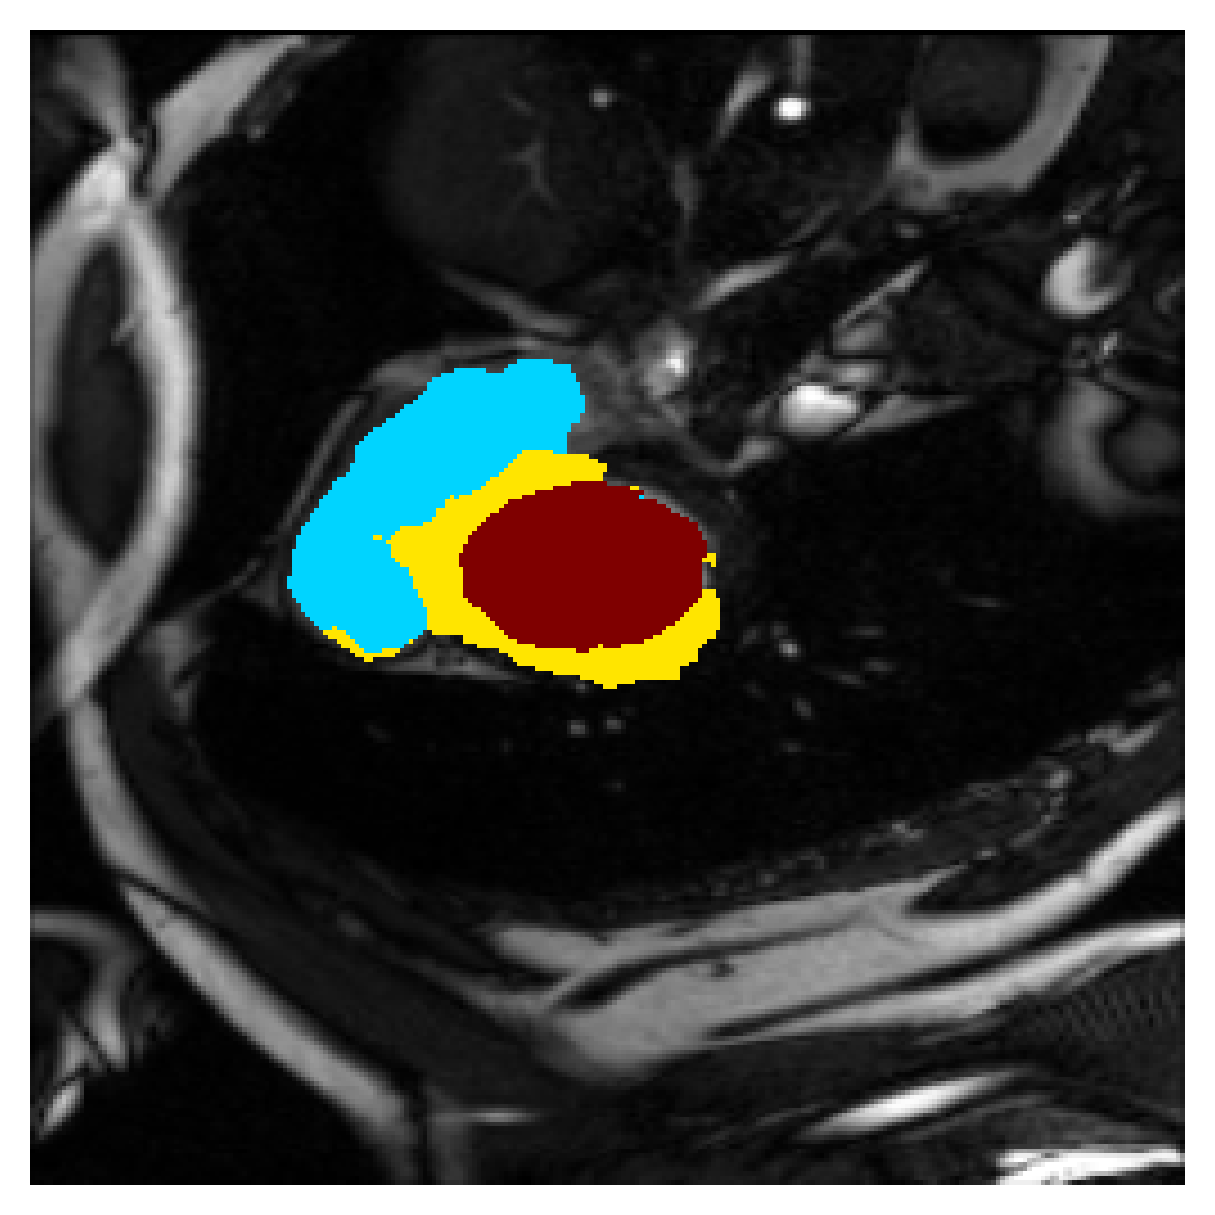

Qualitative comparison

In Figure 6 we provide qualitative results on a number of randomly chosen test set slices. Upon visual inspection, we can observe that training with the intensity-aware distances (particularly with and ) follows the image gradients better and is better at recovering the underlying shape than the Euclidean version. The CRF-loss seems to recover the shape of the myocardium and left ventricle to some extent, but fails entirely on the right ventricle.